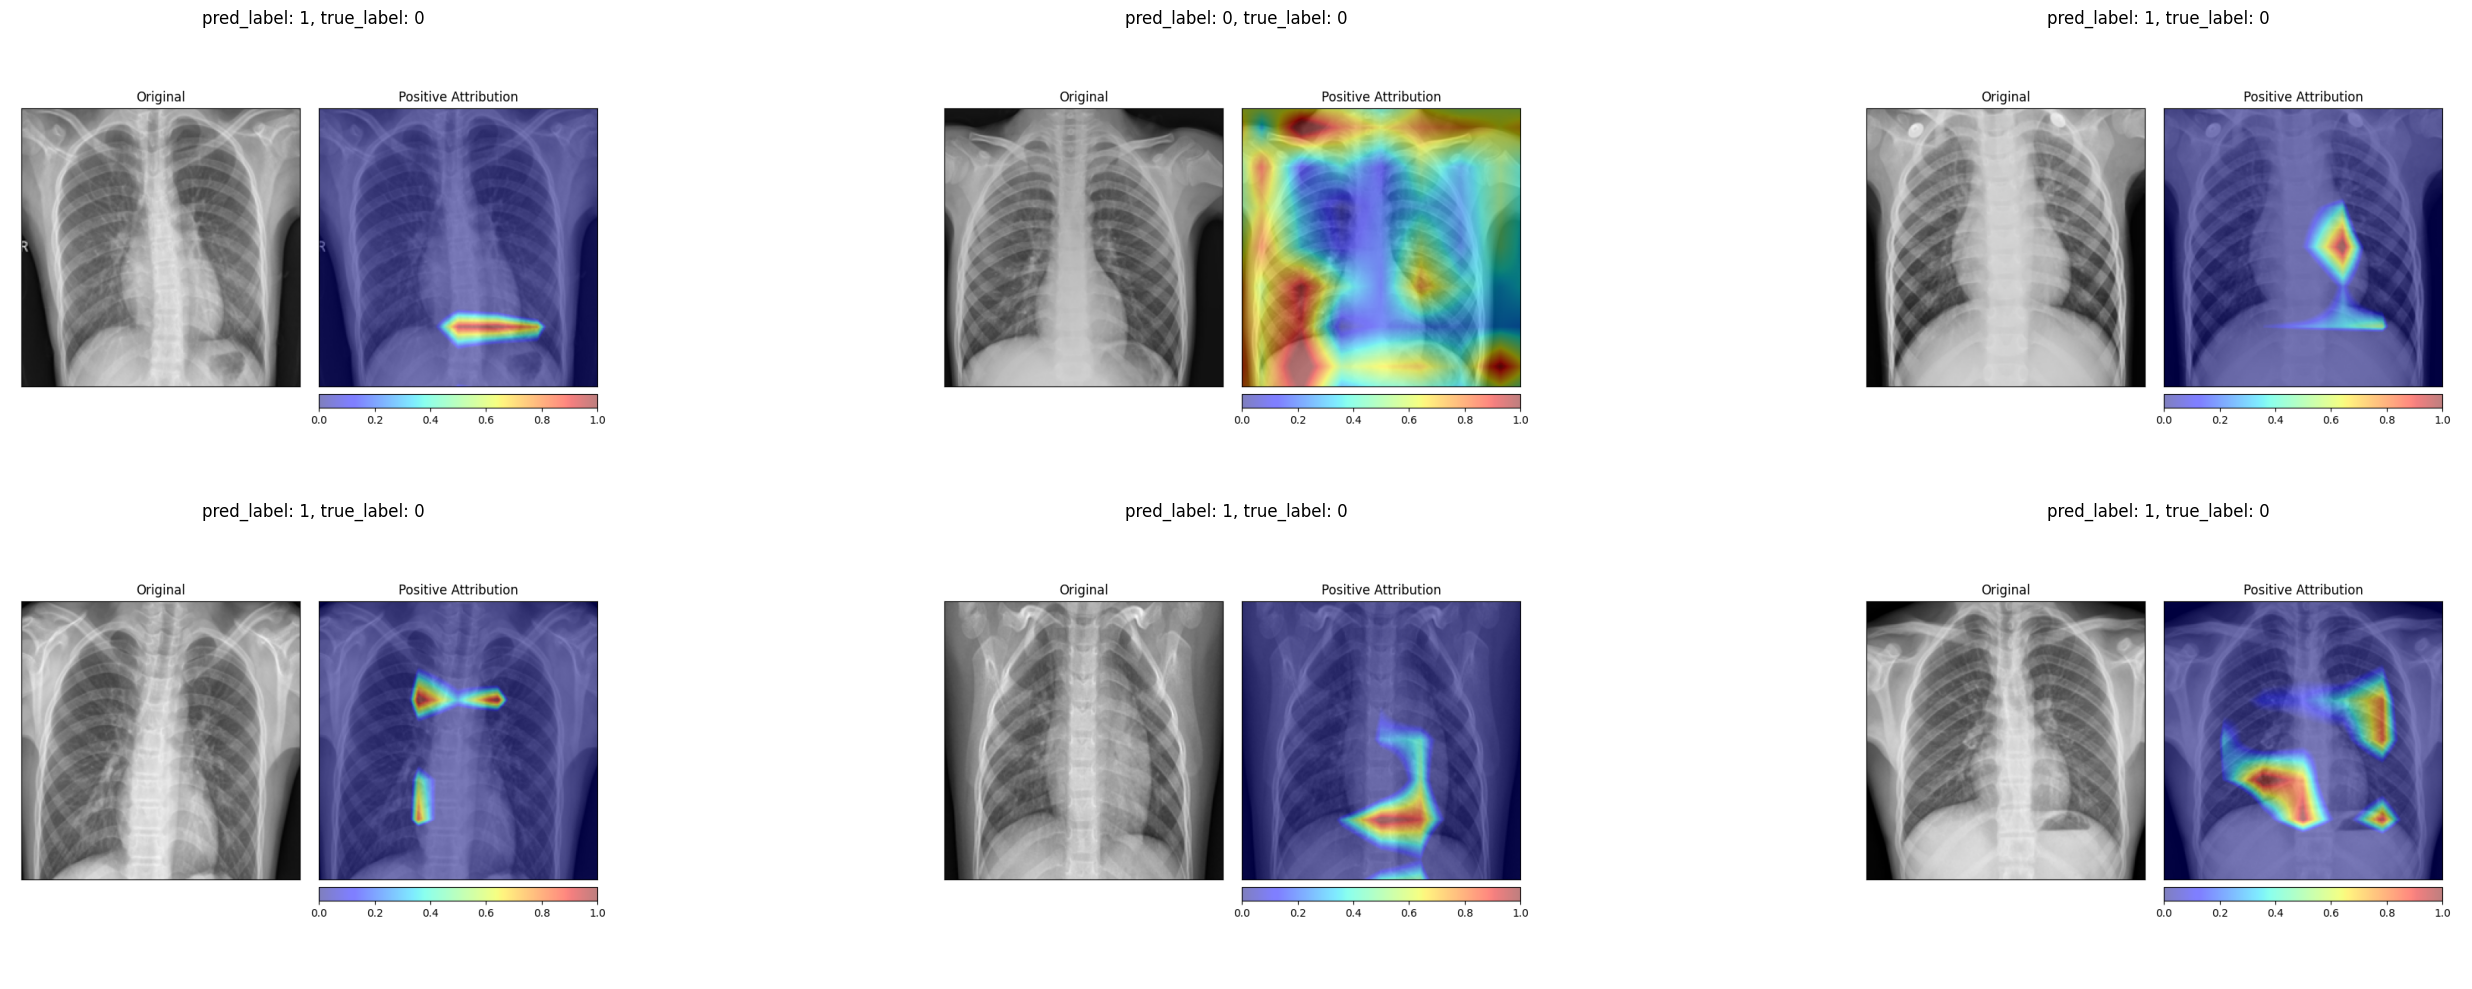

We retrain the same ResNet-50 architecture on the pneumonia dataset with randomly permuted training labels for 200 epochs. As expected, the model’s balanced accuracy drops to 0.52, essentially random chance. The Integrated Gradients maps for the permuted-label model look qualitatively different from those of the properly trained model. The attributions for healthy and diseased patients become indistinguishable, with both showing a similar scattered pattern that outlines anatomical structures without any class-specific focus.

Integrated Gradients on truly healthy patients (permuted-label model)

Integrated Gradients on truly diseased patients (permuted-label model)

The Grad-CAM maps change even more dramatically. The permuted-label model produces much smaller, more fragmented activation regions that no longer correspond to clinically meaningful areas of the lung.

Grad-CAM on truly healthy patients (permuted-label model)

Grad-CAM on truly diseased patients (permuted-label model)

Both methods pass the data randomization test. The attribution maps change substantially when the model is trained on meaningless labels, confirming that they reflect the model’s learned decision function rather than low-level image properties. This is an important validation step that is often overlooked when deploying explainability tools in practice.